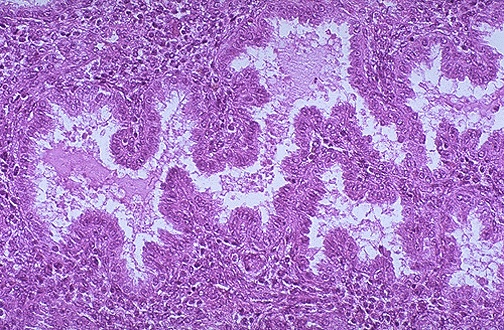

| This is normal secretory endometrium with stellate glands with intraluminal secretions, seen at medium power. Following ovulation, estrogen levels rise and support the secretory pattern, which is typically 14 days long. If implantation of a fertilized ovum does not occur, the secretory phase will be followed by a menstrual phase. |